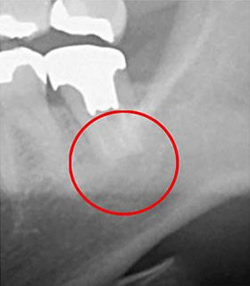

下の画像をご覧ください。

この画像はデンタルレントゲンとCT画像の比較となります。

丸を付けた部分が問題の箇所ですが、デンタルレントゲンだと、この丸の部分に黒い色がついていませんので、問題個所を見落としてしまう可能性があります。

問題部位が発見できなければ当然治療を行うことはできません。

根管治療において「可視化できるか否か」。これは治療の成否を左右する大切なことです。